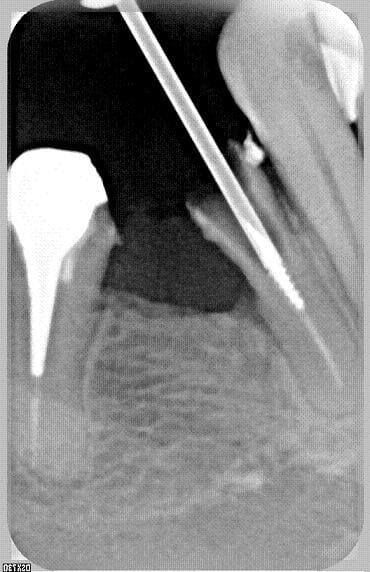

si la fraise est assez longue pour que la tete de turbine ne bloque pas sur 34-36, et si on reste bien dans l'axe....

pour masseran c'est cela, sur une 35 en plus, avoue qu'on te gate!!!!

bin , c'etait juste pour rendre service a phical que j'ai desobturé la dent et cassé puis aleser un peu le screw post, suis serviable moi madame...

oui la dent est toujours là, inlaycore et coiffe, classique et sans rien de special